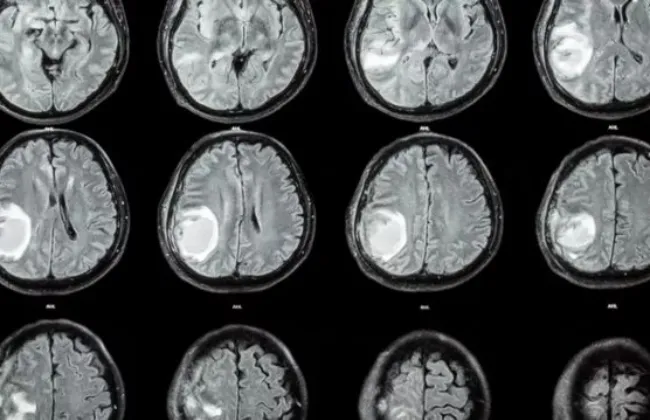

شخص أطباء الأعصاب في الصين شابًا يبلغ من العمر 19 عامًا بمرض الزهايمر، ما جعله أصغر شخص

يتم تشخيصه بهذه الحالة على الإطلاق فى العالم، بحسب موقع "ساينس ألرت".وبدأ المراهق يعاني من تدهور الذاكرة

في سن 17 عامًا تقريبًا، وتفاقمت الخسائر المعرفية على مر السنين

أظهر تصوير دماغ المريض انكماشًا في الحُصين، الذي يشارك في الذاكرة، وألمح سائله النخاعي إلى

علامات شائعة لهذا الشكل الأكثر ....